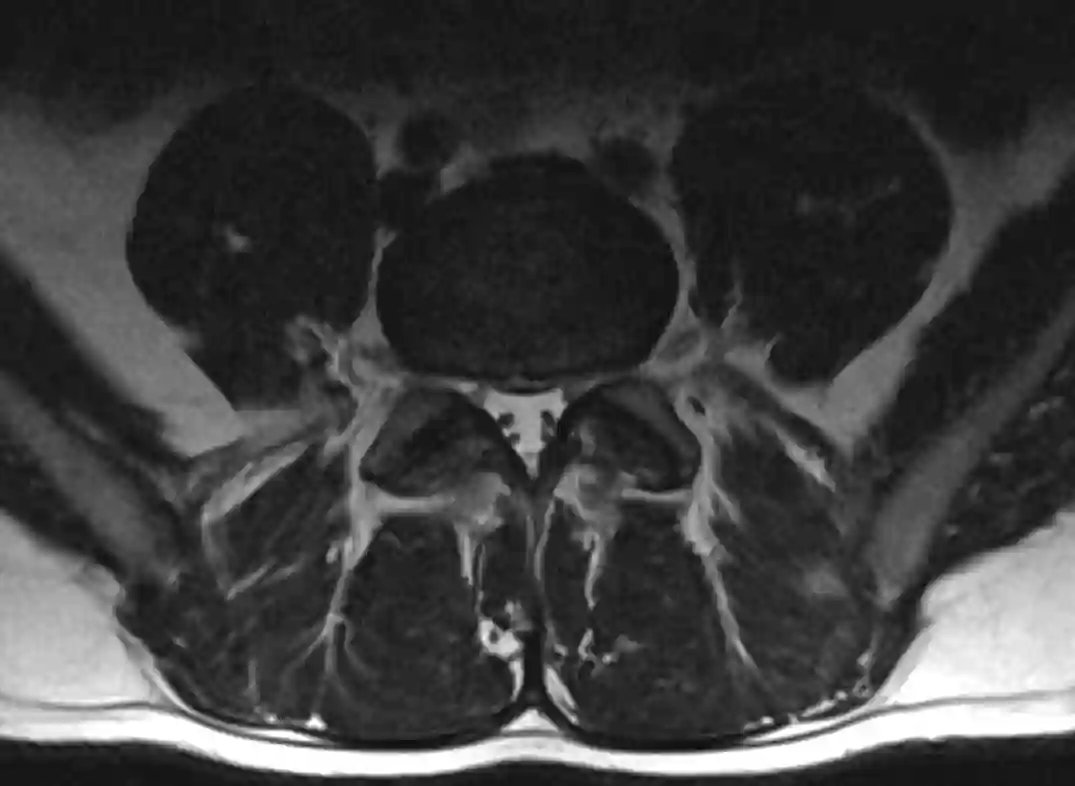

Lumbale Bandscheiben im MRT

Darstellung der Bandscheiben der lumbalen Wirbelsäule in einem sagittalen MRT Bild